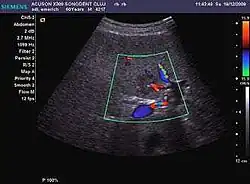

It is the most common liver tumor with a prevalence of 0.4 – 7.4%. It is generally asymptomatic but also can be associated with pain complaints or cytopenia and/or anemia when it is very bulky. It is unique or paucilocular. It can be associated with other types of benign liver tumors. Characteristic 2D ultrasound appearance is that of a very well defined lesion, with sizes of 2–3 cm or less, showing increased echogenity and, when located in contact with the diaphragm, a "mirror image" phenomenon can be seen. When palpating the liver with the transducer the hemangioma is compressible sending reverberations backwards. Doppler exploration reveals no circulatory signal due to very slow flow speed. CEUS investigation has real diagnosis value due to the typical behavior of progressive CA enhancement of the tumor from the periphery towards the center. The enhancement is slow, during several minutes, depending on the size of hemangioma and on the presence (or absence) of internal thrombosis. During late (sinusoidal) phase, if totally "filled" with CA, hemangioma appears isoechoic to the liver. Deviations from the above described behavior can occur in arterialized hemangiomas or those containing arterio-venous shunts. In these cases, differentiation from a malignant tumor is difficult and requires other imaging procedures, follow up and measurements of the tumor at short time intervals.[4]